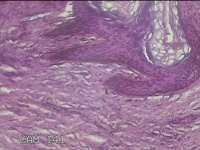

左侧会阴部皮下结节

性别

女

年龄

45岁

临床诊断

皮下结节

一般病史

发现左侧会阴部皮下结节2年余,伴近日局部隐痛不适。

标本名称

大体所见

灰白暗红色结节0.8x0.7x0.3cm一个,表面糜烂。

图1